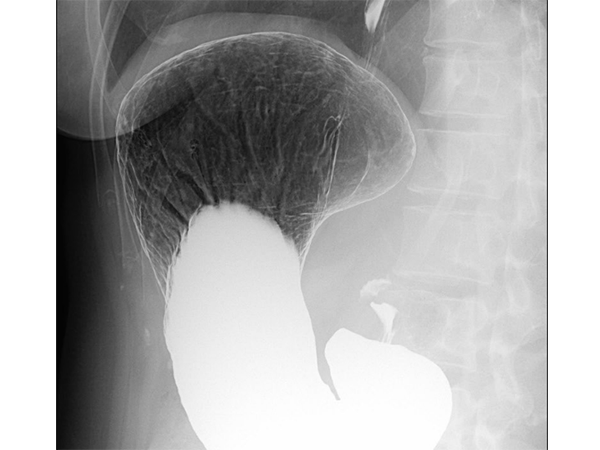

バリウムと発泡剤を飲んでいただき、食道、胃、十二指腸などの病気を調べる検査です。検査時間は5~10分程度で、胃全体の形や大きさ、病変の有無、広がりなどを調べることができます。